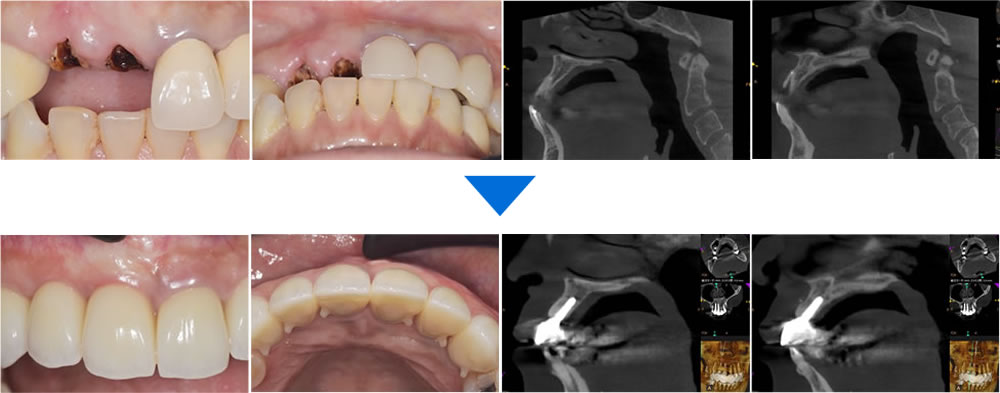

こちらの患者さまは、過去に治療してかぶせ物を装着していた前歯の違和感を主訴に来院されました。当該歯を検査したところ、歯根の部分まで虫歯が進行しており、保存不可能と診断しました。

患者さまと相談し、抜歯即時埋入インプラントで咬み合わせを回復する計画を立てました。

適切なインプラント治療を実施するため、CTによる精密検査を行い、顎骨の状態をはじめ、インプラントの埋入位置や埋入角度を確認します。

良好な予後、前歯部分の審美性を考慮し、保存不可能な前歯を抜歯した後、同日に骨造成法を併用してインプラントを埋入しました。

CT画像にてインプラントと顎骨の結合を確認後、製作した最終的な上部構造を装着して治療完了となりました。

治療前後の比較